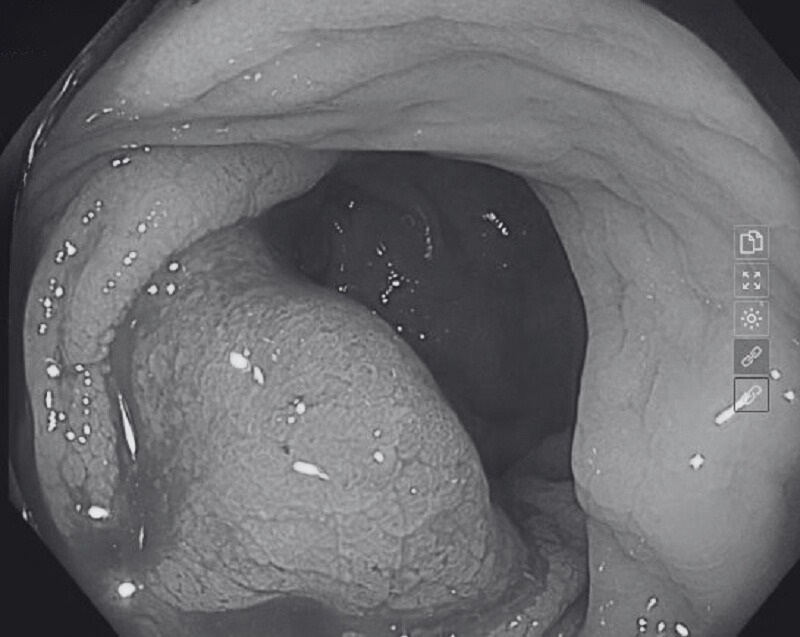

Nội soi trực tràng ống mềm là phương pháp phổ biến được áp dụng để kiểm tra đường tiêu hóa. Bác sĩ sẽ sử dụng một ống nội soi mềm có đèn và camera đưa vào trực tràng thông qua hậu môn. Hình ảnh bên trong trực tràng và đường tiêu hóa sẽ hiển thị rõ nét, chi tiết trên màn hình máy tính đã được kết nối với camera nội soi. Thông qua đó, bác sĩ sẽ đưa ra kết luận chính xác về vấn đề bệnh nhân đang gặp phải.

Những trường hợp nội soi trực tràng thường áp dụng với bệnh nhân bị ung thư đại - trực tràng, loạn sản, dị sản, tổn thương tiền ung thư, polyp,… Khi thực hiện nội soi, bác sĩ có thể kết hợp sinh thiết, tức là lấy mẫu ở vùng bị tổn thương để kiểm tra dưới kính hiển vi.

Nội soi trực tràng là phương pháp thăm dò chức năng hỗ trợ bác sĩ thăm khám, kiểm tra đường tiêu hóa